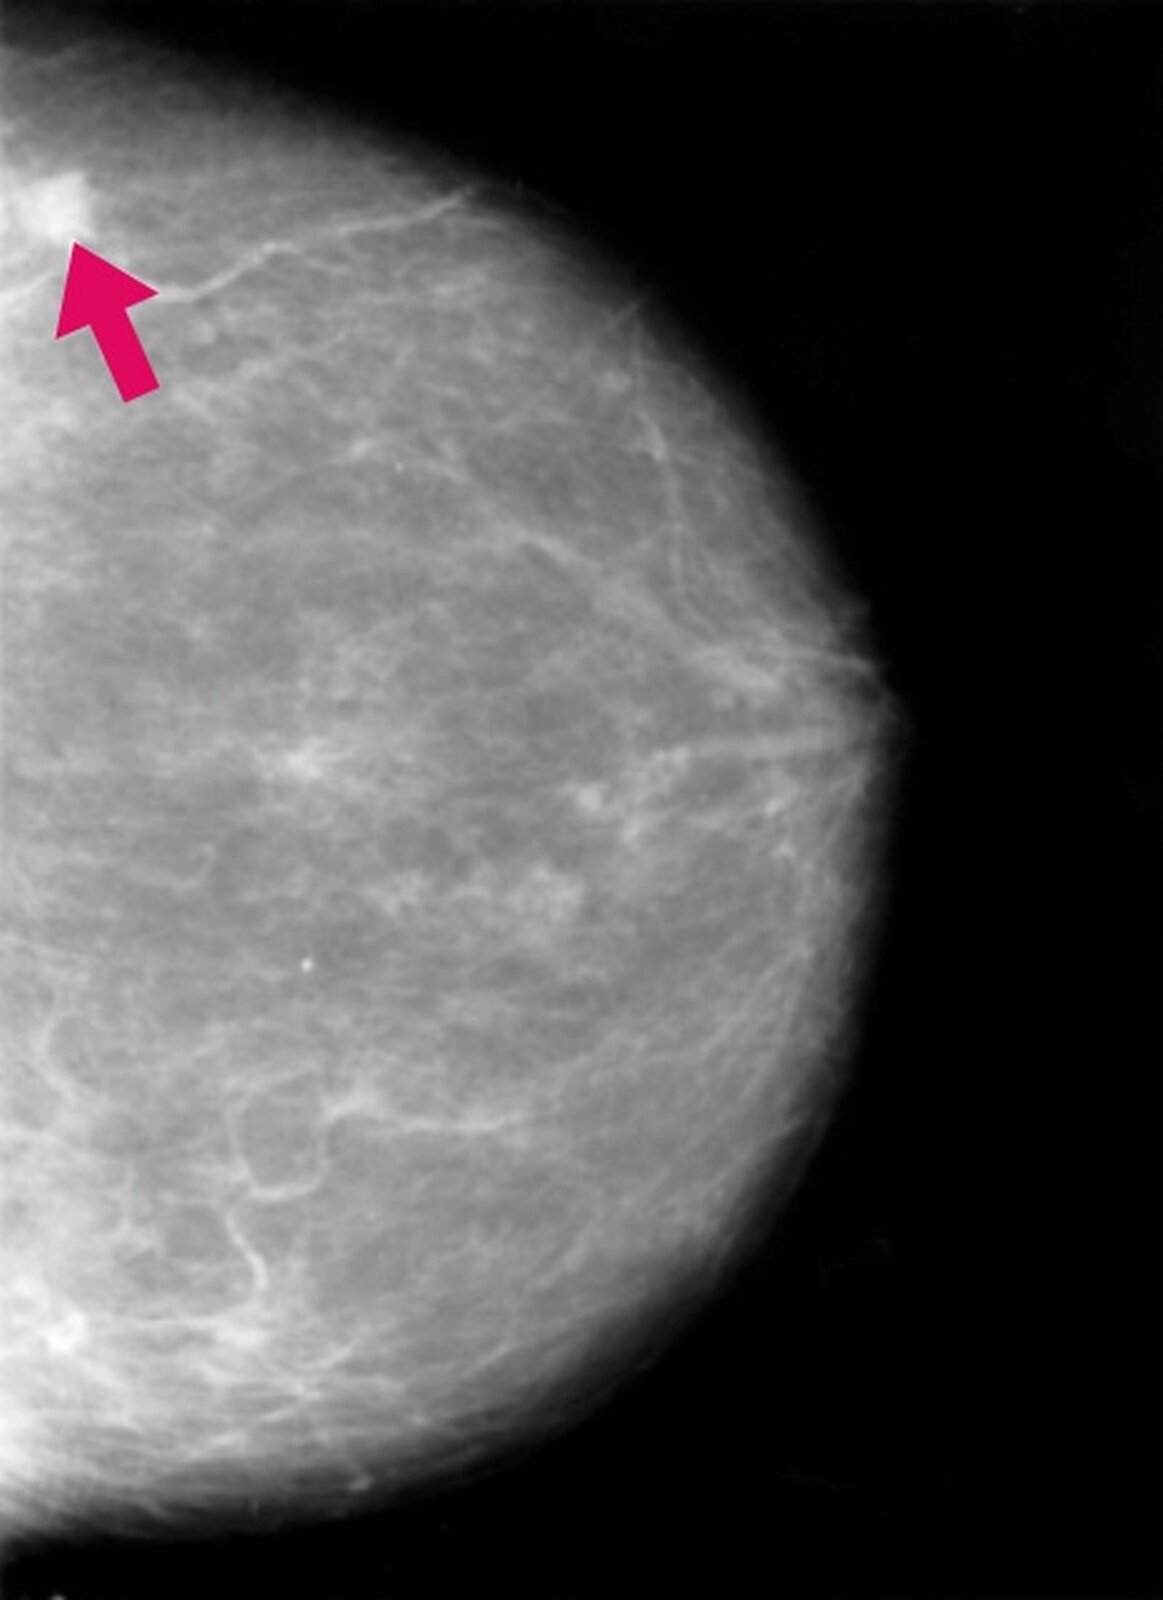

Rak piersi (rak sutka)

Przyczyna: zmiany w materiale genetycznym.

Zakażenie: nie można zakazić się od drugiej osoby

Objawy: twardość piersi, guzek lub wgłębienie w piersi zmiana kształtu piersi, zmiany skórne piersi, zmiany w wyglądzie brodawki sutkowejbrodawki sutkowej, wyciek wydzieliny z brodawki sutkowej, powiększenie węzłów chłonnych w okolicy piersi.